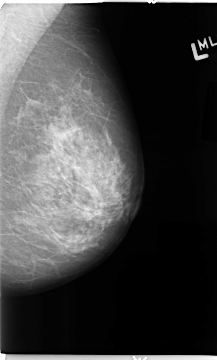

B_3116_1.LEFT_CC

LEFT_CC LINES 4792 PIXELS_PER_LINE 2664 BITS_PER_PIXEL 12 RESOLUTION 50 NON_OVERLAY